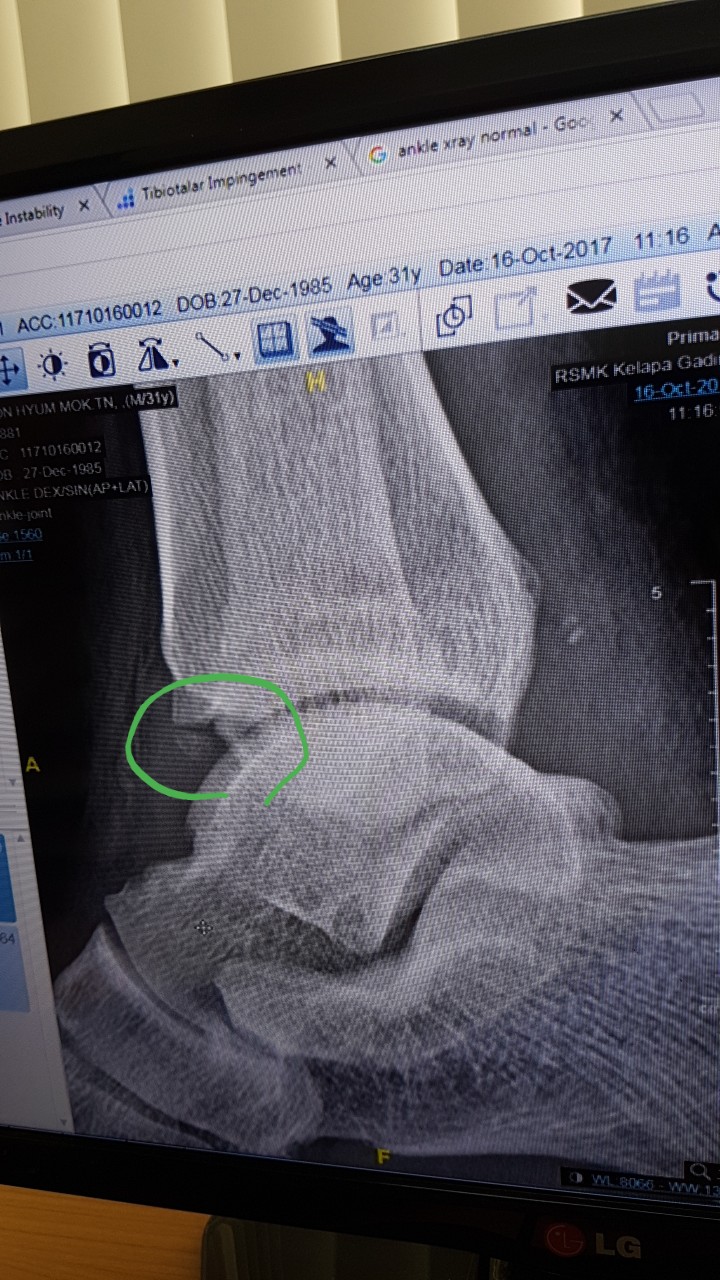

안녕하세요저는 인도네시아에서 현재 근무를 하고 있습니다.다름이아니라 2주전에 운전을 오래하고 골프를 치고 난 후 그다음부터 오른 발목이 시큰시큰 아프더니 결국 붓기가 올라 아직도 붓기가 빠지지 않고 있습니다.그리하여 한의원도 가보고 진통소염제 등 약도 먹어보다 어제 xray를 찍고 검사를 했는데 엑스레이 결과를 보고 Tibiotalar impingement 라고 합니다.수술을 해야한다는데 사실 외국이라 의학용어를 정확하게 몰라 다시한번 여쭙고자 합니다.필요시 한국에서 검사하고 수술할생각도 있어 한번 확인 부탁 드립니다아래의 사진에 동그라미 친부분을 제거해야한다는데 부탁드립니다어떤 수술을 해야하며 얼마나 걸릴까요 ? 제가 외국에서 근무를 해서 휴가기간을 정해야합니다.빠른답변 기다리겠습니다. ㅇ

사용자 등록 이미지 |

286.0K

|

497 Download(s)